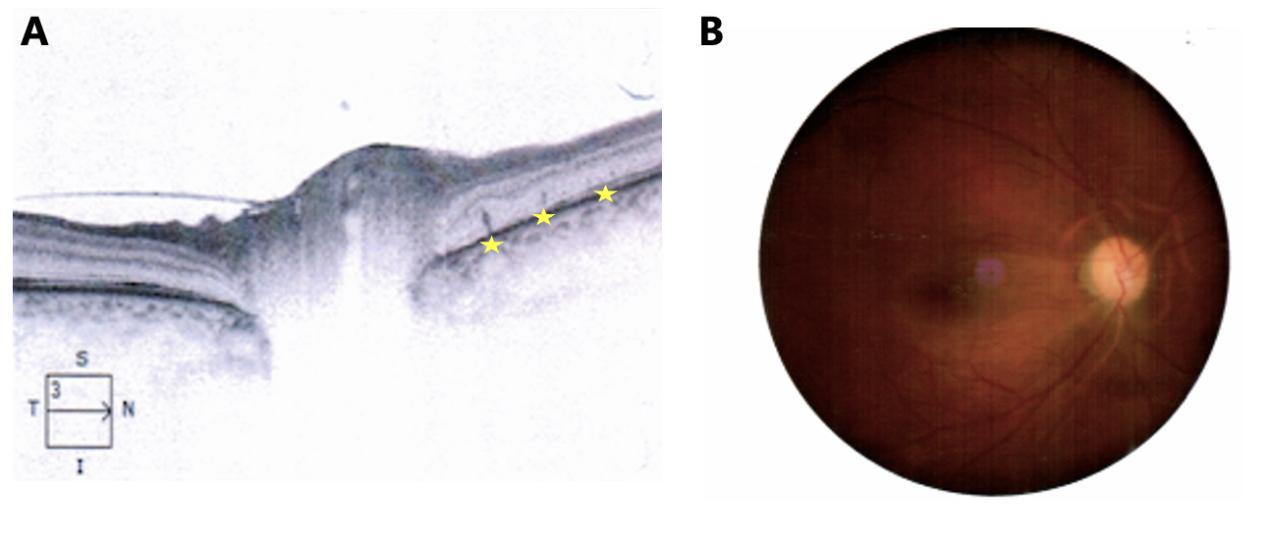

图6 例2患者治疗后右眼OCT及眼底表现

Figure 6 Post-treatment changes in case 2 (right eye)

图6 治疗后右眼OCT及眼底表现

(A)治疗1个月后,右眼视盘周围视网膜外层可见数个钉状突起高反射病灶(黄色星形指示);(B)驱梅治疗3个月后,右眼视盘 水肿消退,边界尚清,色泽苍白。

(A) OCT at 1-month follow-up: Focal spicule-like hyperreflective lesions in the peripapillary outer retina (yellow asterisks). (B) Fundus at 3 months after anti-syphilitic treatment: resolved disc edema with relatively distinct margins and pallor, indicating optic atrophy.

进一步追问病史,患者否认猫狗接触史及冶游史;皮肤、神经系统等查体未见明显异常;至此病因仍然不明确,充分沟通后给予多西环素联合利福平治疗猫抓病,皮肤科会诊给予氨苄青霉素肌注治疗梅毒,同时给予中等剂量激素抗炎、营养神经及改善循环等对症治疗。1个月后复查OCT:视盘周围RPE层可见不规则中高反射凸起病灶(见图6-A),而这是梅毒感染眼部较为特征的临床表现,支持梅毒相关视神经炎的诊断。此外,猫抓病视神经炎一般预后良好,且有一定自限性,本例患者虽然经过1月充分抗巴尔通体感染及抗炎治疗,但视力仍然下降,这与眼猫抓病的病程特点不太相符。最终,本病例的诊断确定为梅毒相关视神经炎。因此,继续给予驱梅及联合激素治疗,治疗3月后,视盘水肿消退,边界尚清,但色泽苍白(见图6-B),视力0.63。